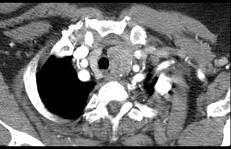

问题 40岁,女,发现颈部肿块,随吞咽上下移动,触之无搏动,咳嗽、气喘一周,请结合CT图。检查选择最可能的诊断 ( )

选项 A、无名动脉伸展扭曲 B、淋巴瘤 C、胸内甲状腺瘤 D、无名动脉瘤 E、胸腺瘤

答案 C